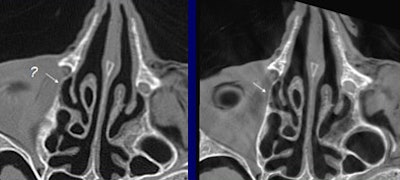

Both modalities produced diagnostic images, but fpVCT produced a significantly higher average sum score (60.8) compared to MDCT (41.5) (p < 0.02). In particular, structures such as the stapedial muscle and the bony walls of the facial nerve canal were much more clearly displayed in fpVCT, Bartling said.

| The flat-panel VCT images of the skull base at right were rated significantly higher in image quality compared to 16-slice MDCT images of the same regions at left, by two readers rating 21 features independently. Images (from top to bottom) include stapes and ovale window niche (above), facial nerve canal (below), maxillofacial region, and implanted microscrews (bottom). All images courtesy of Dr. Sönke Bartling. |

"The same holds true for small and especially thin structures within the maxillofacial region, for example the medial limitation of the orbital cavity is much better delineated in flat-panel-based volume CT," Bartling said. And the technique produces fewer metal artifacts, he added.